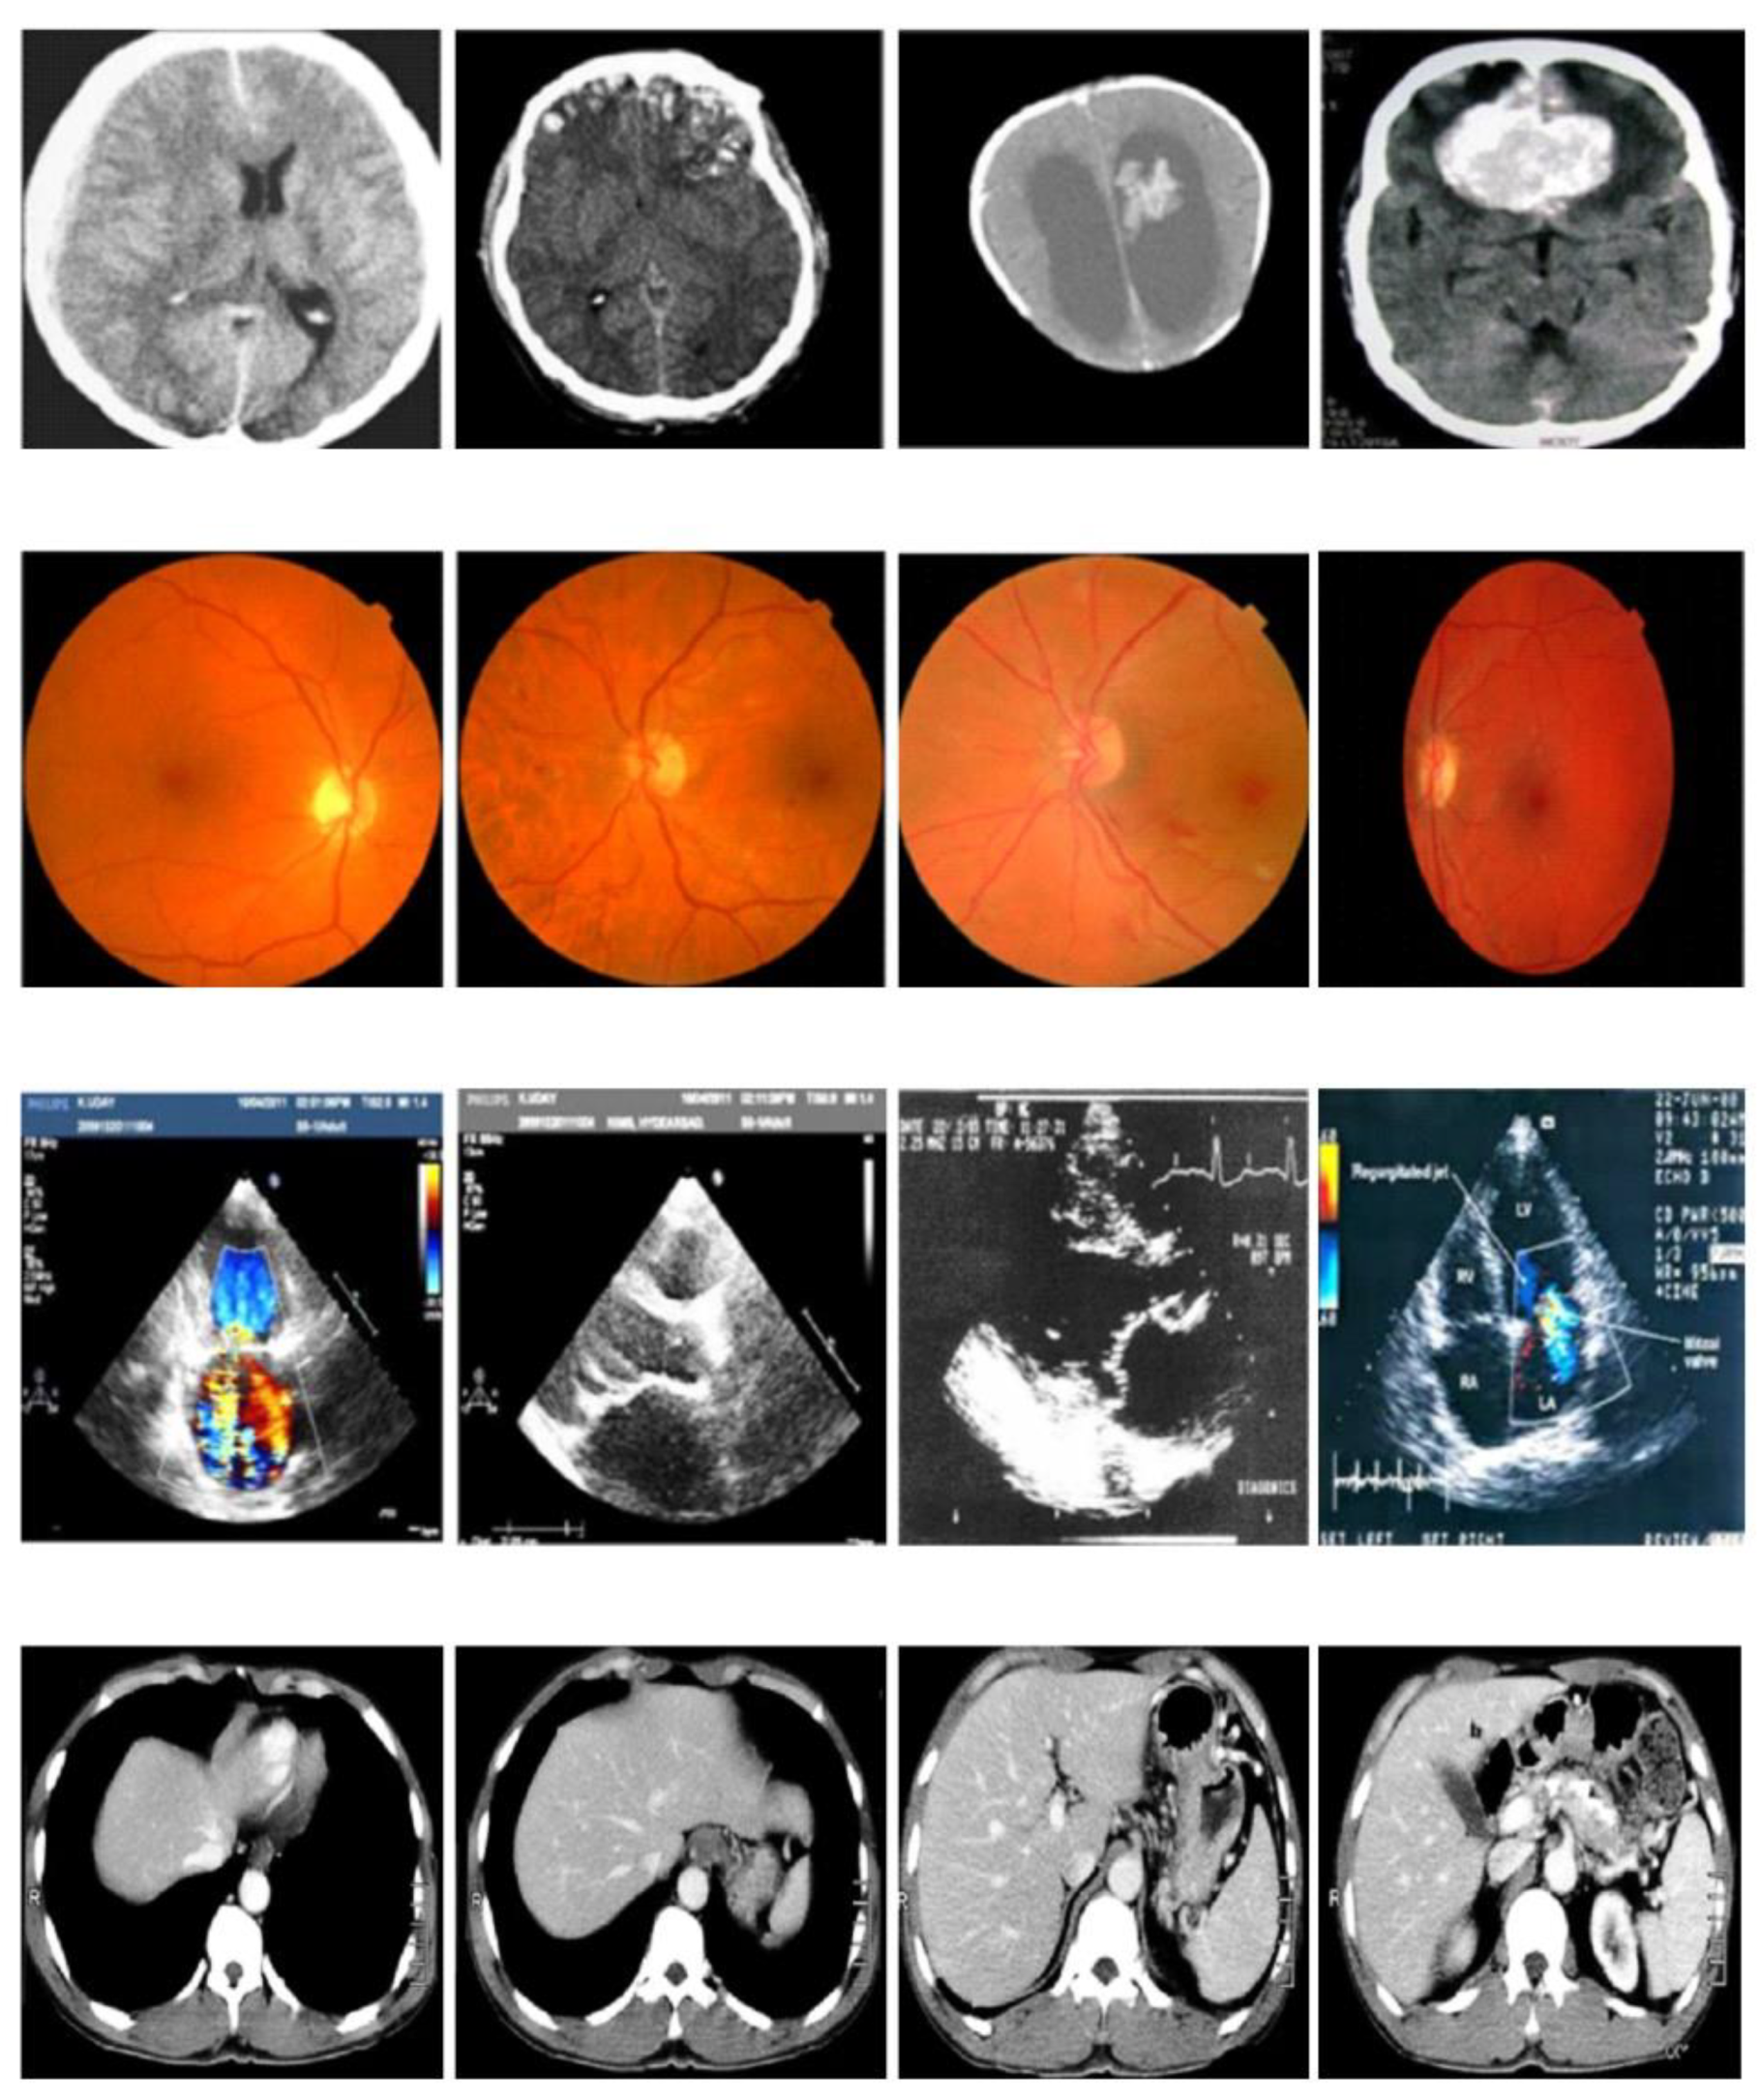

4. Results and Discussion

4.1. PSNR Results Analysis

4.2. MSE Results Analysis

4.3. BER Results Analysis

4.4. SSI Results Analysis

4.5. Correlation Coefficient Results Analysis

4.6. CPU Run Time Results Analysis

4.7. Encryption Time Results Analysis

4.8. Results Comparison of Proposed and Existing Lightweight Crypto Algorithm